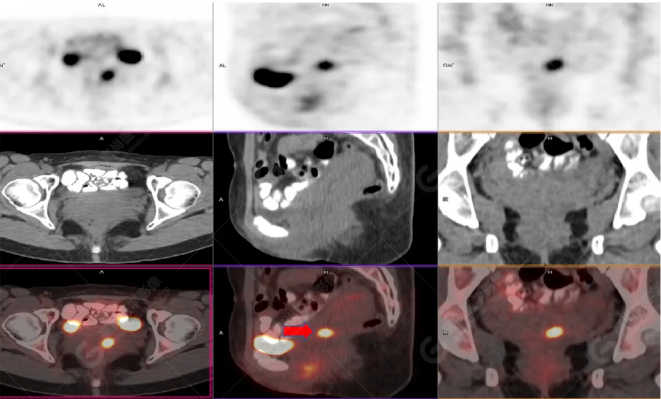

女性 67歲 因背痛查體,糖尿病11年。腫瘤標(biāo)記物:CEA 6.4↑,AFP、CA125、CA199正常。外院MR檢查:胸11椎體-附件左份異常信號,增強環(huán)狀強化,骨原發(fā)?轉(zhuǎn)移?感染?PET/CT影像圖

胸椎溶骨性骨質(zhì)破壞,F(xiàn)DG環(huán)狀代謝增高,SUVmax為4.0。

左側(cè)乳腺一軟組織結(jié)節(jié),F(xiàn)DG代謝增高,SUVmax為2.6。

最終診斷:左側(cè)乳腺癌伴胸椎單發(fā)骨轉(zhuǎn)移。